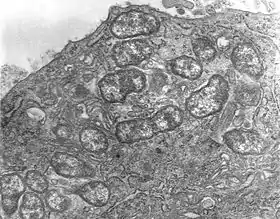

التيفوس الأكالي أو حُمَّى تسوتسوغامُوشي هو شكل من أشكال التيفوس التي تسببها الطفيل داخلي الخلايا التسوتسوغاموشية الأورينتية (Orientia tsutsugamushi)، من عائلة الريكتسيات والذ تم عزله والتعرف عليه للمرة الأولى في اليابان عام 1930.[1][2]